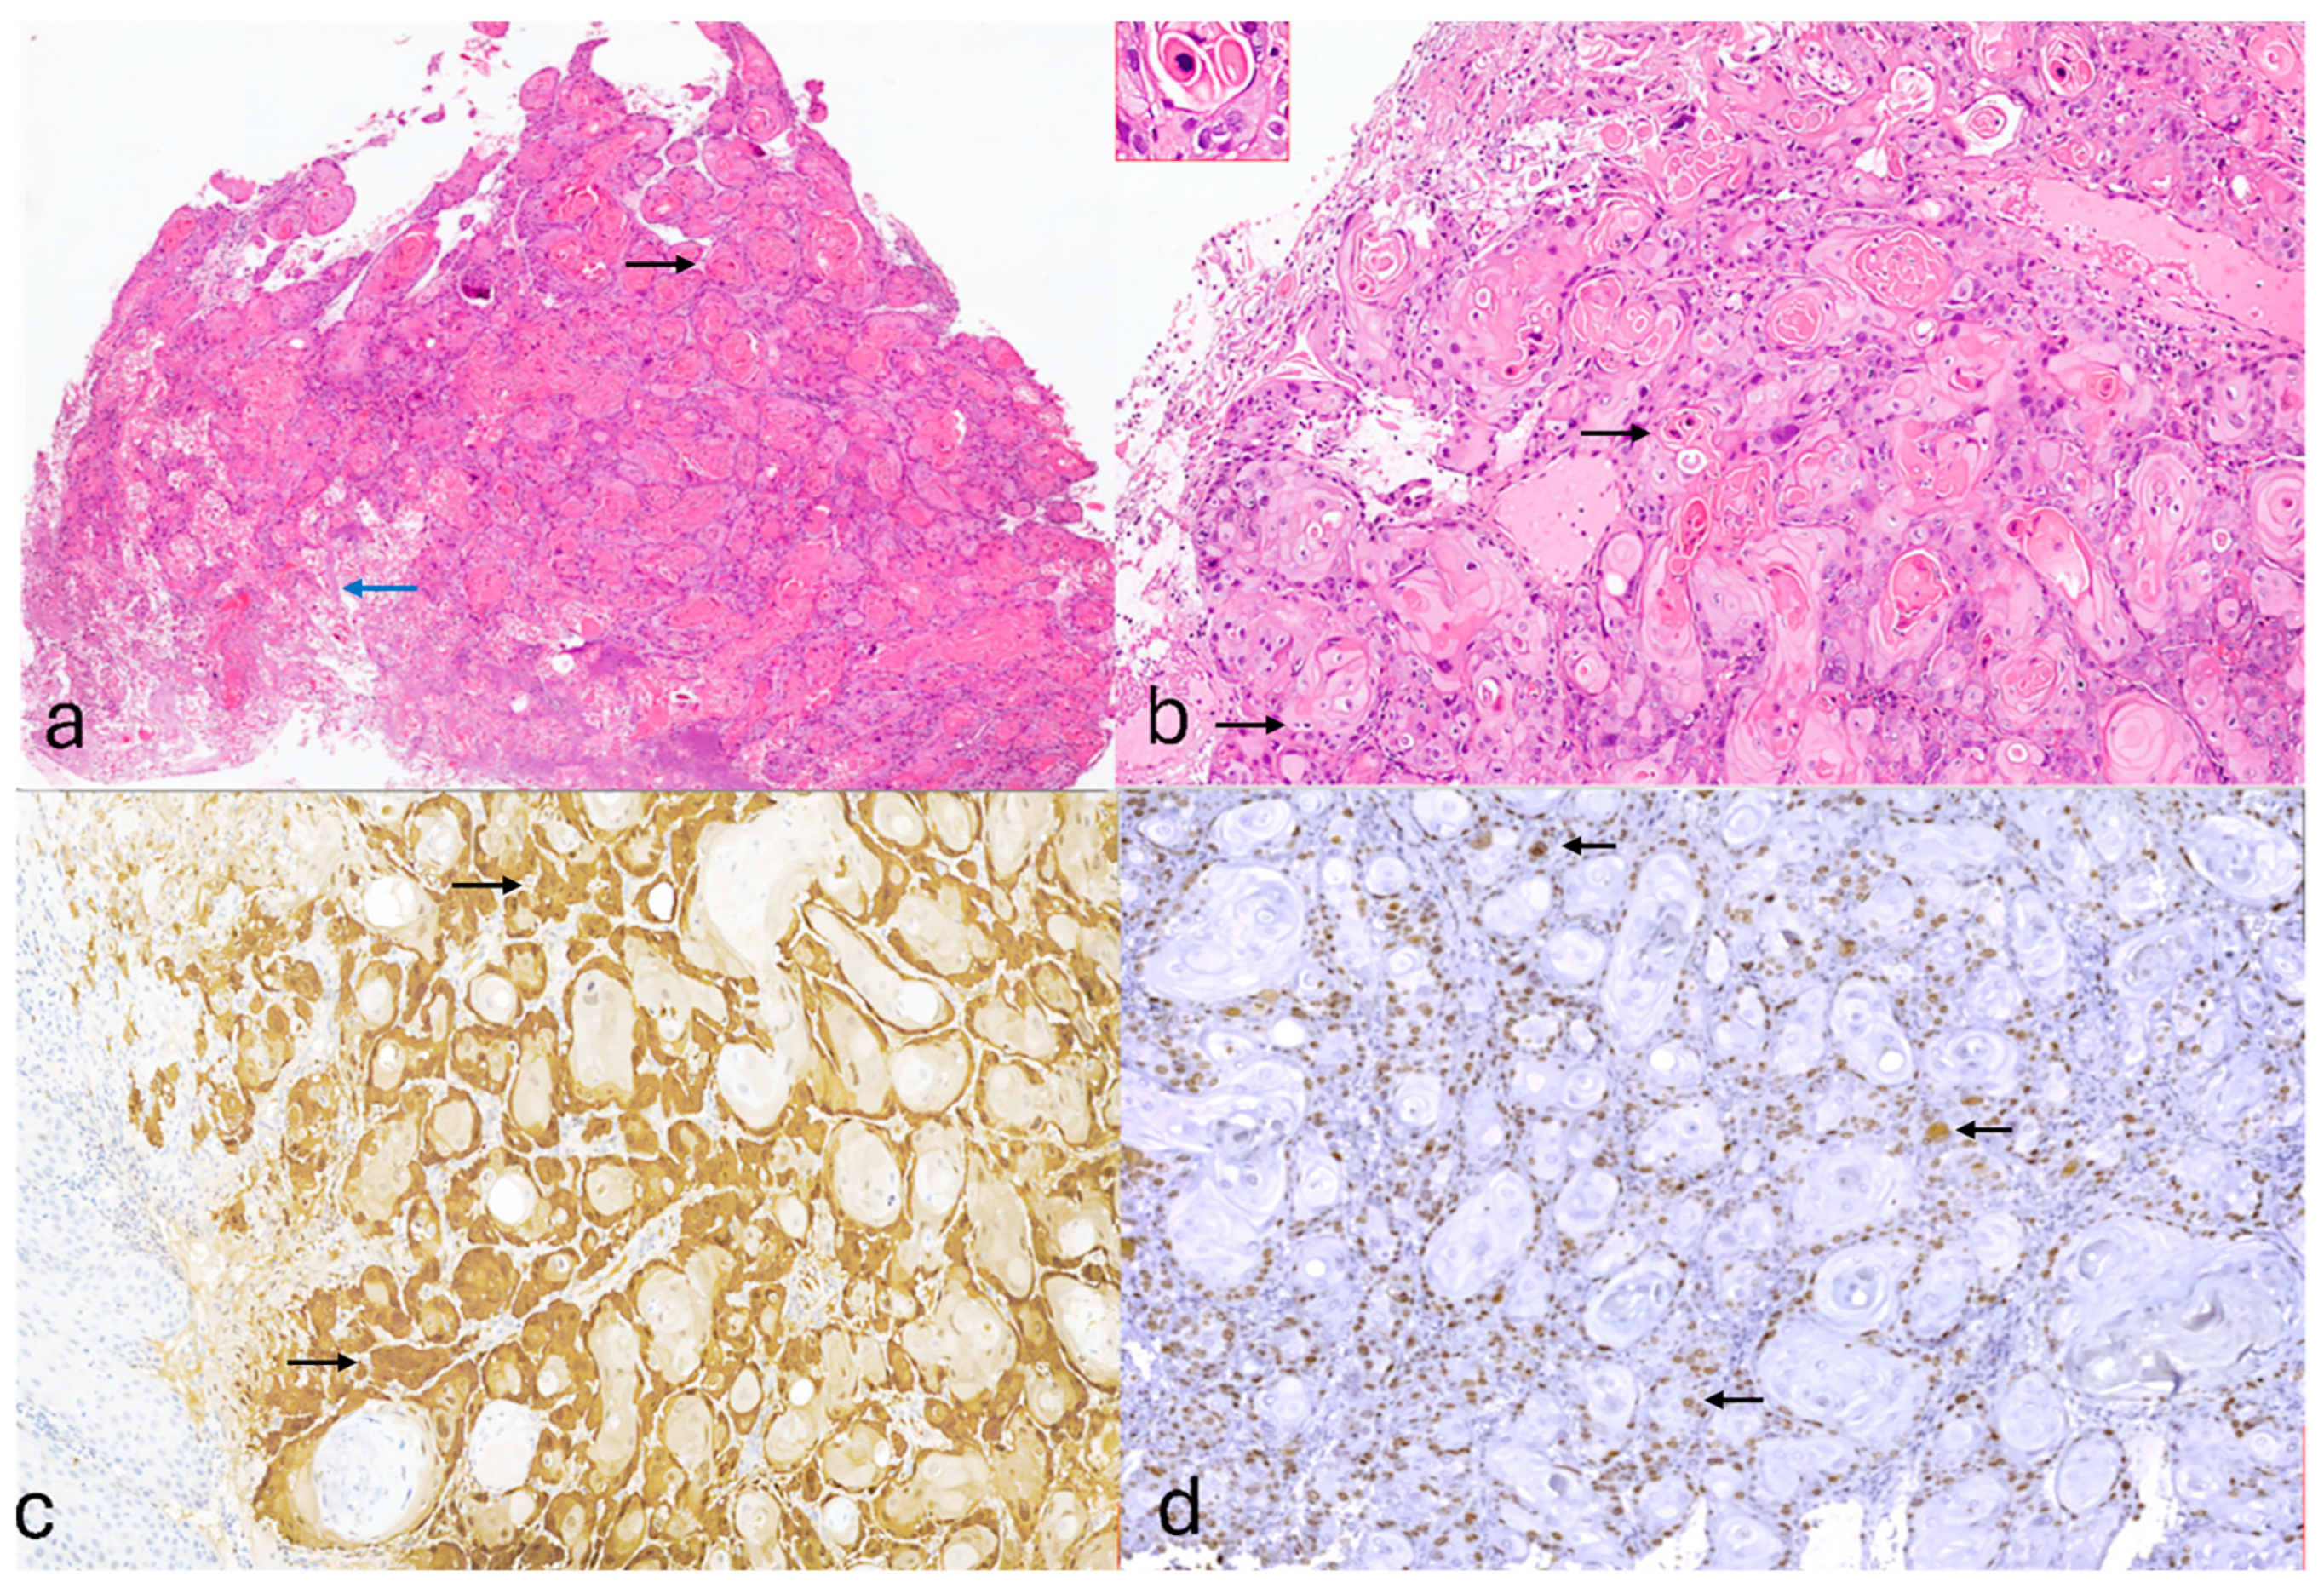

2. Case Presentation

3. Discussion